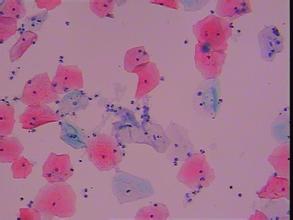

什么是念珠菌?

念珠菌是一种真菌,它常寄生于人的皮肤、口腔、阴道和肠粘膜等处,当机体免疫机能低下或正常寄居部位的微生态环境失调,容易引起念珠菌病。

念珠菌是酵母霉菌的一种菌,患病往往是性病产生比较高,就是传播率。人人都会有菌,也有好也有坏,比如常在菌。